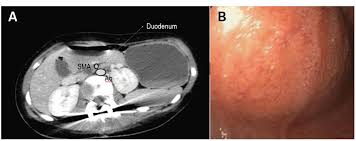

Axial Ct Section Demonstrating The Anatomy Of Sma Syndrome Download Scientific Diagram

Acute Gastric Dilation Caused By Superior Mesenteric Artery Syndrome Postgraduate Medical Journal

Superior Mesenteric Artery Syndrome As A Cause Of Acute Pancreatitis Bmj Case Reports